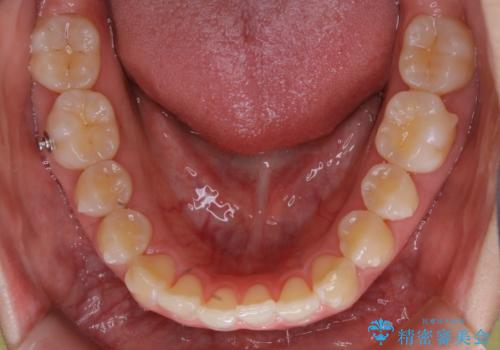

- 初診時、前歯のガタつきを主訴にご来院されました。

精密検査の結果奥歯の噛み合わせのズレからくる前歯のガタつきであることが分かり、患者様と相談した結果、全体をしっかりと治療することをご選択なさったので奥歯から動かして噛み合わせと見た目の両方を治す治療プランとなりました。

下顎の歯は幸いガタつきが少なかったため、下顎を基準とし構成する方針としました。